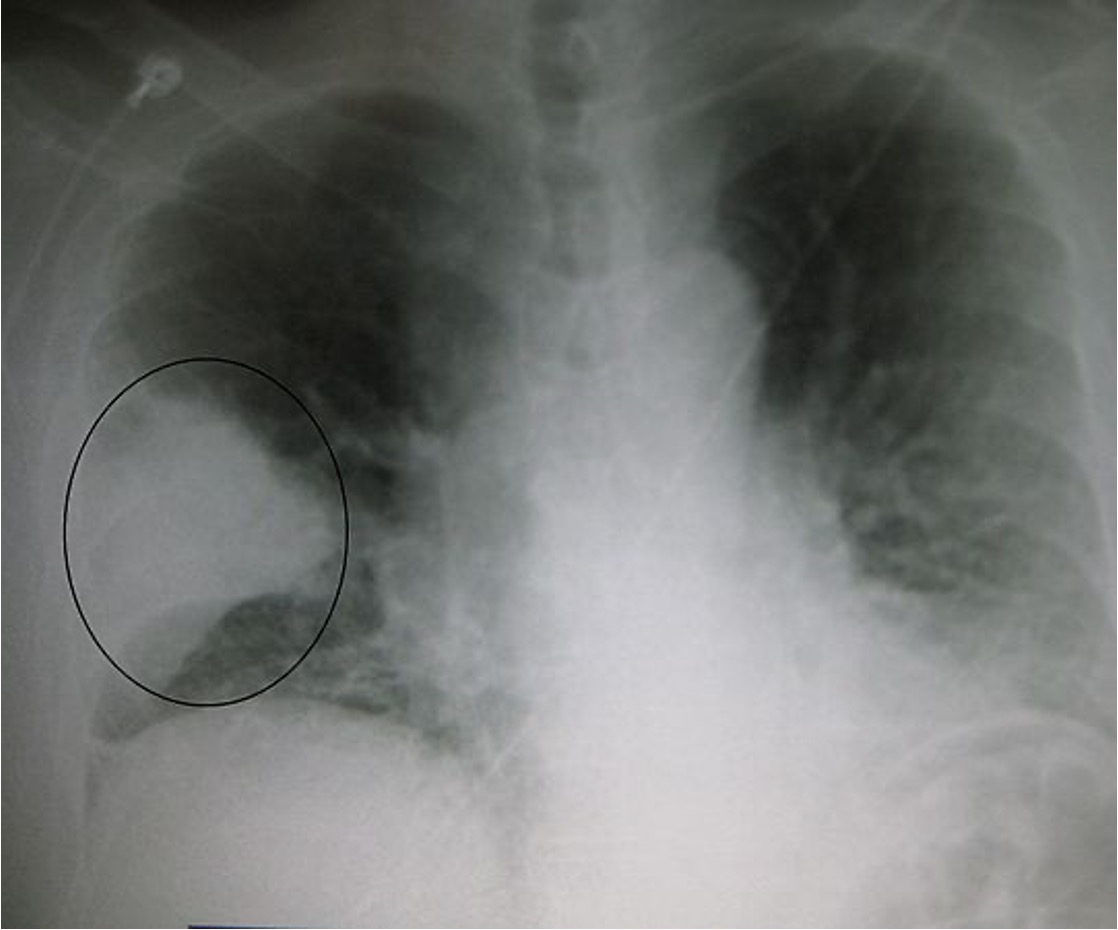

what is seen on this xray?

pneumonia

what type of CAP would the xray look worse than the pt?

typical

what CXR findings are seen w/ CAP?

lobar consolidations

interstitial infiltrates

cavitations